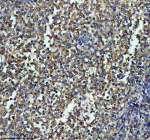

Immunohistochemical staining of ITGB7 using anti-ITGB7 antibody. ITGB7 was detected in a paraffin-embedded section of human lymphoma tissue. Heat mediated antigen retrieval was performed in EDTA buffer (pH 8.0, epitope retrieval solution). The tissue section was blocked with 10% goat serum. The tissue section was then incubated with 1:50 rabbit anti-ITGB7 antibody overnight at 4oC. Peroxidase Conjugated Goat Anti-rabbit IgG was used as secondary antibody and incubated for 30 minutes at 37oC. The tissue section was developed using an HRP secondary and DAB substrate.